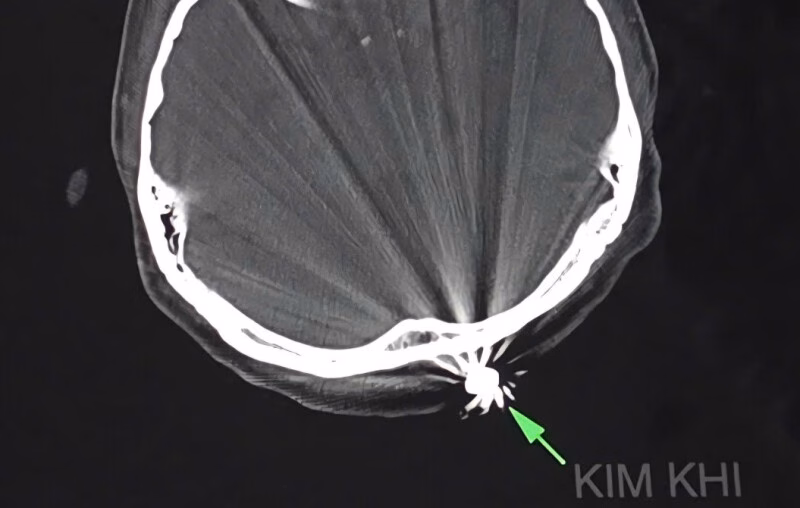

Ngày 28/7 vừa qua, một sự cố đáng tiếc đã xảy ra khi chị D.T.K.T, 40 tuổi, ngụ tại TP Cần Thơ, bị trúng đạn trong lúc làm vườn tại nhà riêng. Viên đạn đã găm vào vùng chẩm của chị, gây ra tình trạng chảy máu nhiều. Ngay sau đó, chị T. được đưa đến Bệnh viện đa khoa Trung ương Cần Thơ cấp cứu trong tình trạng đau đầu dữ dội, với một vết thương nhỏ khoảng 1cm ở vùng chẩm đã cầm máu.

Nhận được tin báo, các bác sĩ tại Khoa Ngoại thần kinh của bệnh viện đã nhanh chóng tiến hành phẫu thuật để lấy dị vật và xử trí tổn thương. Để đảm bảo an toàn và hiệu quả, các bác sĩ đã quyết định mở rộng vết mổ khoảng 3cm. Sau khoảng 45 phút, ca phẫu thuật đã thành công, viên đạn kích thước 0,5×0,3cm đã được lấy ra thành công. Điều令人 bất ngờ là viên đạn chỉ xuyên qua lớp da bên ngoài và chạm nhẹ vào xương chẩm mà không gây tổn thương đến não và các cấu trúc lân cận.